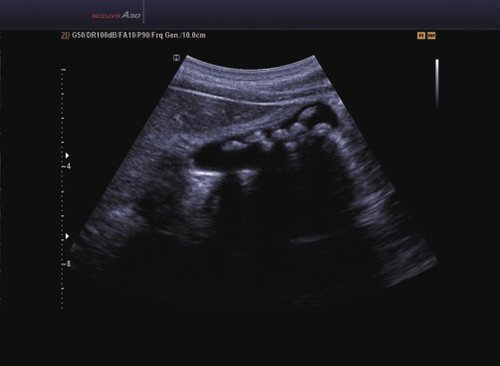

Das Samsung Accuvix A30 ist ein hochwertiges Ultraschallsystem, das mit seiner 3D-Technologie herausragende Ergebnisse ermöglicht. Das Sonographiegerät besitzt 5 Sondenanschlüsse und ist mit 20 unterschiedlichen Schallköpfen kompatibel. Mit dem A30 können Schallköpfe vom Typ Konvex, Mikrokonvex, 3D-Konvex, CW, Phased Array, Linear und Endokavitär verwendet werden. Bei zwei der Sonden handelt es sich um S-VUE Ultraschallsonden, die durch ihre höhere Bandbreite noch feinere Scans erzeugen.

6 SC1-6 Konvex 1-6 Abdomen, Fetal, Frauenheilkunde und Geburtshilfe, Niere, Notfallmedizin

8 C1-4 Konvex 1-4 Abdomen, Frauenheilkunde und Geburtshilfe, Kontrast

12 V2-6 3D Konvex 2-6 Abdomen, Frauenheilkunde und Geburtshilfe

13 V4-8 3D Konvex 4-8 Abdomen, Frauenheilkunde und Geburtshilfe